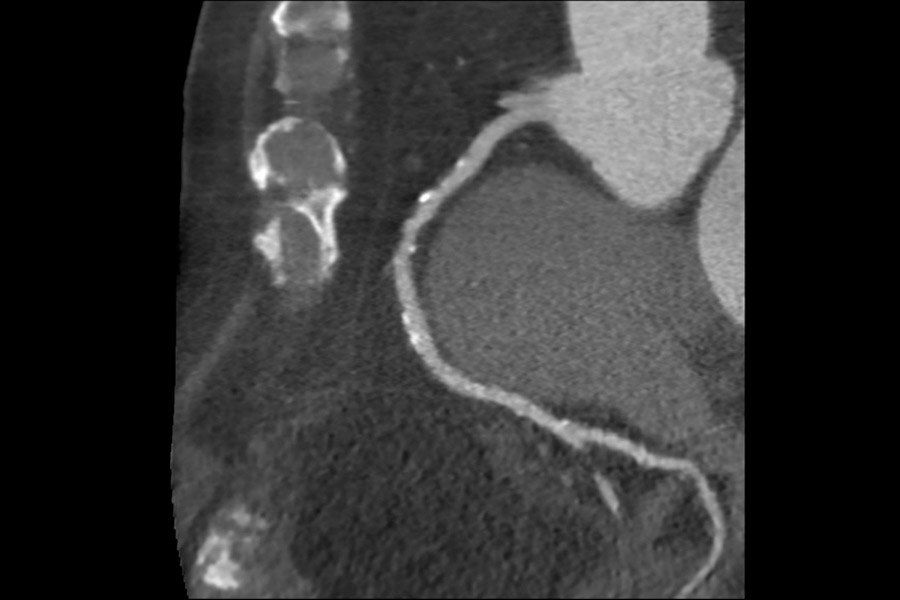

Calcified Plaque on 118 kg patient, 63 BPM, BMI 40.3